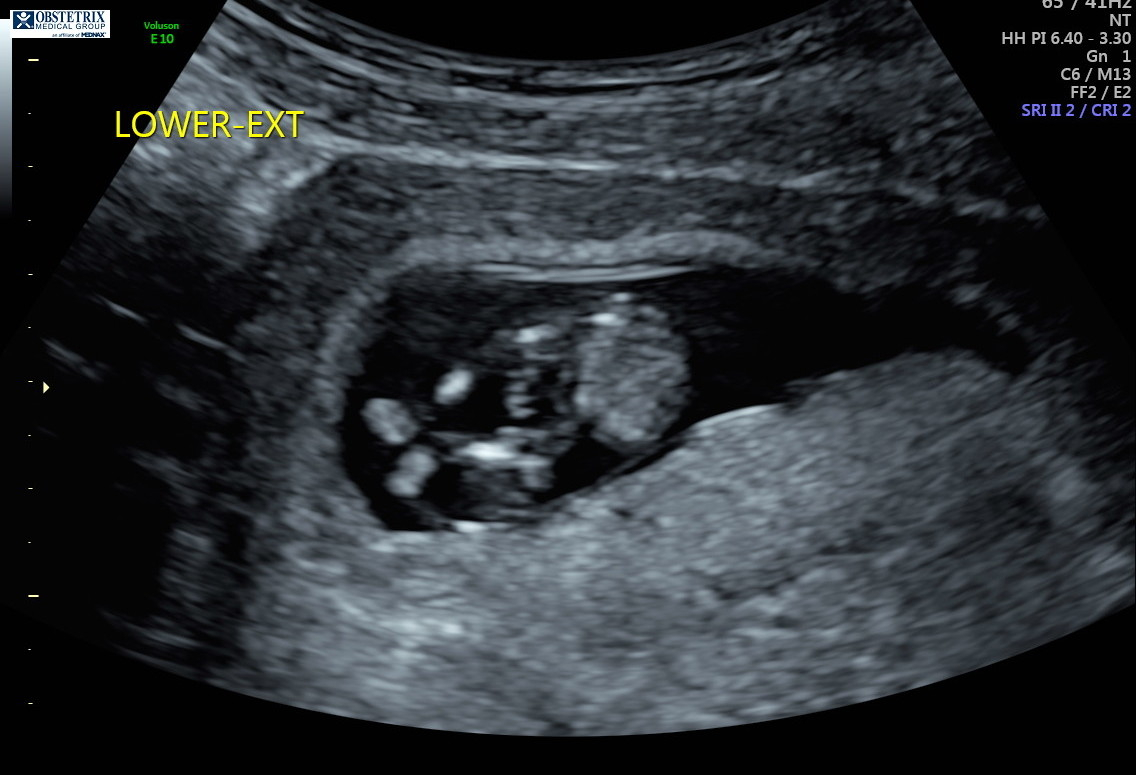

Hello! The photo is from my 12 week ultrasound. I’ve been reading up on the nub theory because I’m dying to know the sex, but I can’t decide if it looks more girly or boyish. Any thoughts are appreciated!!!!

“Experts” on the nub theory my friend. Yes, I have talk to doctors about it. Yes, some do believe in the nub theory while others are afraid to guess because they are afraid to guess wrong and upset anyone which makes sense. No, it is not always accurate and if you try the nub theory generally you know not to take to it too seriously until the anatomy scan. Also this theory will not hurt the baby so no harm done. But if you can’t handle the possibilty of a wrong guess then don’t even try asking for a guess. It’s for fun. Have you read up on it even? The nub sits flat with the back if it’s a girl and it’s angled up from the back if it’s a boy. I have 2 girls and 1 boy so I am pretty sure it’s not “luck” just really good scans! The “experts” on the nub theory have guessed correctly with my ultrasound pictures. I have also done the NT scans which is around the right time to make a guess with the nub about 11-13 weeks I believe. The doctor agreed that it can be accurate if done properly. You must have a perfect nub picture ( a full body side view of fetus without their back curled during 11-13 weeks) to get a pretty accurate guess. Notice my use of guess? Yes, still 50/50 and yes, doctors still get the anatomy scan wrong too so you can’t be 100% sure until birth if you are want total accUracy. Do some reading up. I found it very interesting when I had my first child. But it is called a theory for reason.

“Experts” on the nub theory my friend. Yes, I have talk to doctors about it. Yes, some do believe in the nub theory while others are afraid to guess because they are afraid to guess wrong and upset anyone which makes sense. No, it is not always accurate and if you try the nub theory generally you know not to take to it too seriously until the anatomy scan. Also this theory will not hurt the baby so no harm done. But if you can’t handle the possibilty of a wrong guess then don’t even try asking for a guess. It’s for fun. Have you read up on it even? The nub sits flat with the back if it’s a girl and it’s angled up from the back if it’s a boy. I have 2 girls and 1 boy so I am pretty sure it’s not “luck” just really good scans! The “experts” on the nub theory have guessed correctly with my ultrasound pictures. I have also done the NT scans which is around the right time to make a guess with the nub about 11-13 weeks I believe. The doctor agreed that it can be accurate if done properly. You must have a perfect nub picture

( a full body side view of fetus without their back curled during 11-13 weeks) to get a pretty accurate guess. Notice my use of guess? Yes, still 50/50 and yes, doctors still get the anatomy scan wrong too so you can’t be 100% sure until birth if you are want total accUracy. Do some reading up. I found it very interesting when I had my first child. But it is called a theory for reason.